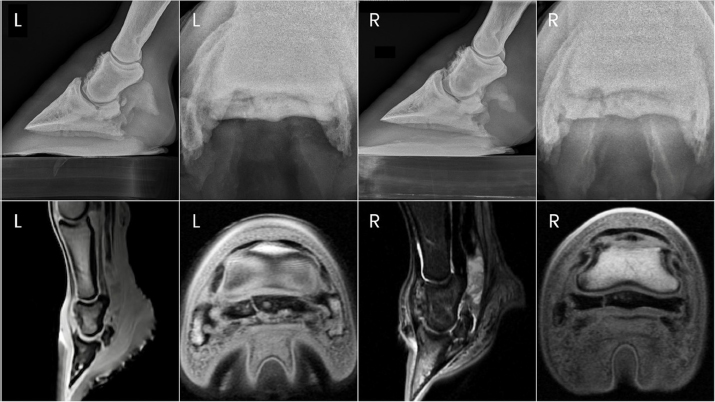

Fig. 4. Ante-mortem radiographs and postmortem MRI images of horse two showing the right forelimb navicular bone fracture and bilateral DDF tendon compromise.

Horse 2 remained comfortable postoperatively with no appreciable lameness until approximately day 129, at which time a mild and inconsistent grade 4/5 RF lameness was noted. On day 136 post-PDN, the gelding was presented for student teaching of radiographic techniques. Radiographs were taken of both front digits, which revealed a parasagittal fracture of the right forelimb navicular bone and mild hyperextension of the right DIPJ (Fig. 4). Ultrasound revealed severe fiber pattern disruption of the DDF tendon suggestive of severe tendinopathy or rupture in the distal pastern region of both the right and left forelimbs. Humane euthanasia was elected due to the severity of the pathology and poor prognosis. Postmortem MRI was performed on both forelimbs revealing marked bilateral navicular bone degeneration with an obliquely oriented complete fracture of the lateral quarter of the navicular bone on the right forelimb, and bilateral severe DDF tendinopathy with almost complete rupture of the DDF tendon at the level of the navicular bone (Fig. 4). Additional findings of note in both forelimbs were significant navicular bursitis with probable bursal adhesions, enthesopathy of the flexor surface of the third phalanx at the DDF tendon insertion site, and impar, collateral sesamoidean ligament, and distal digital annular ligament desmopathy.